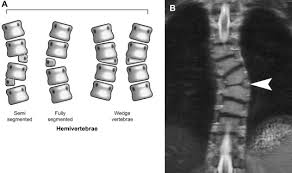

So, if you look at the picture on the right, that is sort of what Thomas X-ray showed in his lower back. Only the top bone comes down much more and is very slanted and the bottom bone is a lot smaller. The small bone piece that is at the arrow is larger and actually coming at you more. This small bone is making a knot in his lower back.

I did ask if physical therapy could help with this hemi vertebrae condition and the answer given was a flat 'no'. Not sure how I feel about that to be honest. I don't know what this means for Thomas' future at this point. The orthopedic surgeon is also concerned about another abnormal vertebrae just below his neck and wants to review that one more closely when we go back in six months. So, that's what I know. I don't have many more answers, but we know a little bit more of what is going on with his spine. We only go back if he appears to be showing pain or I see any other changes like fever, cold chills, etc. Otherwise we will go back in October.